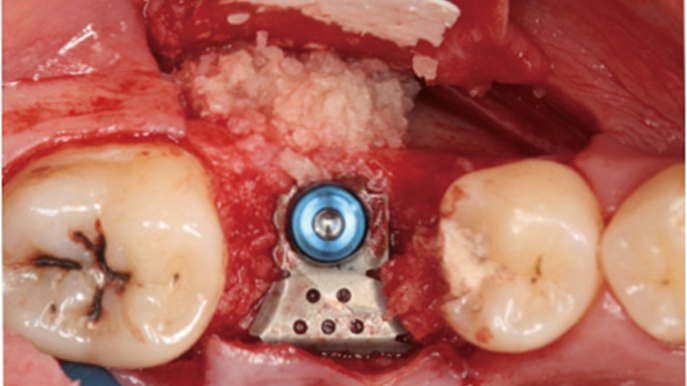

Clinical case: Ridge splitting technique using SmarThor + AnyRidge as expander

- Courtesy of Dr.Kwang-Bum Park, Korea -

AnyRidge, ridge splitting, GBR, Dr. Kwang-Bum Park, mandibular posterior, SmartThor, Mega-Oss, thin ridge, bone regeneration

AnyRidge implant system. SmarThor, Mega-Oss